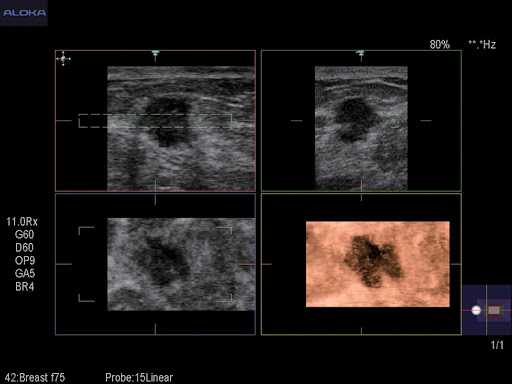

Комплектация универсальной УЗИ системы HITACHI ALOKA ProSound F75 включает массу дополнительных режимов и модулей, включая 3D/4D. Специалист с легкостью сможет подобрать нужный набор опций для решения любых, даже самых сложных задач, чтобы провести детализированное и качественное исследование.

Экспертные функции подойдут для продвинутой диагностики сердечно-сосудистой системы, органов малого таза, вычислений показателей гемодинамики и других узких специализаций. Современные технологии работы с изображениями дают превосходное качество и позволяют извлечь максимум информации. Серошкальная визуализация, допплеровское цветовое картирование кровотока, а также спектральное допплеровское исследование кровотока, которые поддерживает система, позволяют оперативно провести качественные и количественные оценки.

- исследования малых органов

- Эластография компрессионная (опционально)

- Эластография сдвиговой волны с количественным анализом (опционально)

- Анализ эластографии

UST-5415 – Универсальный линейный датчик для исследования сосудов и поверхностных органов. Благодаря широкому диапазону частот, средней апертуре и поддержке множества режимов сканирования датчик зарекомендовал себя, как универсальное решение для большого круга потребностей.